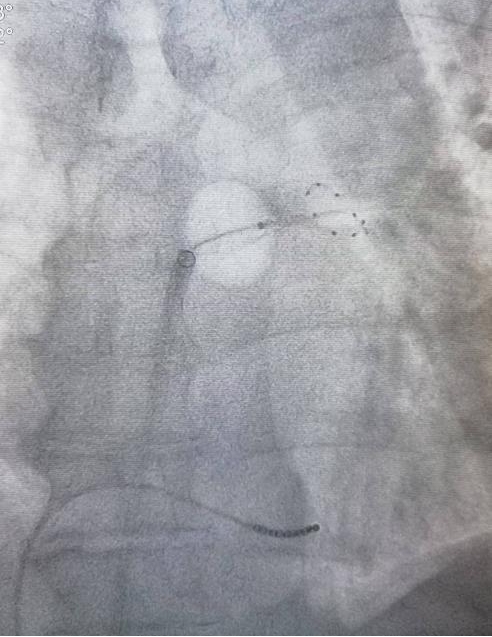

手术过程中,何亚军主任、何勇主任医师首先在患者大腿根部进行穿刺,房间隔穿刺成功后,在DSA引导下,导管精确地定位到病变部位。随后启动冷冻消融设备,将冷冻球囊传递至病变部位。经过一段时间冷冻,病变组织细胞坏死,手术过程顺利。

经冷冻球囊导管消融(CBA)为近年出现的新的消融方法,通过球囊封堵肺静脉,在球囊内释放液态N2O,使周围组织冷冻、细胞坏死形成瘢痕,已成为实现肺静脉隔离的标准方法之一。多项研究均已证明CBA治疗房颤有很好的安全性及有效性,具有学习曲线短、严重并发症少及再住院率低等优势,且CBA在高龄、解剖变异以及心衰的阵发房颤患者中也同样安全有效。